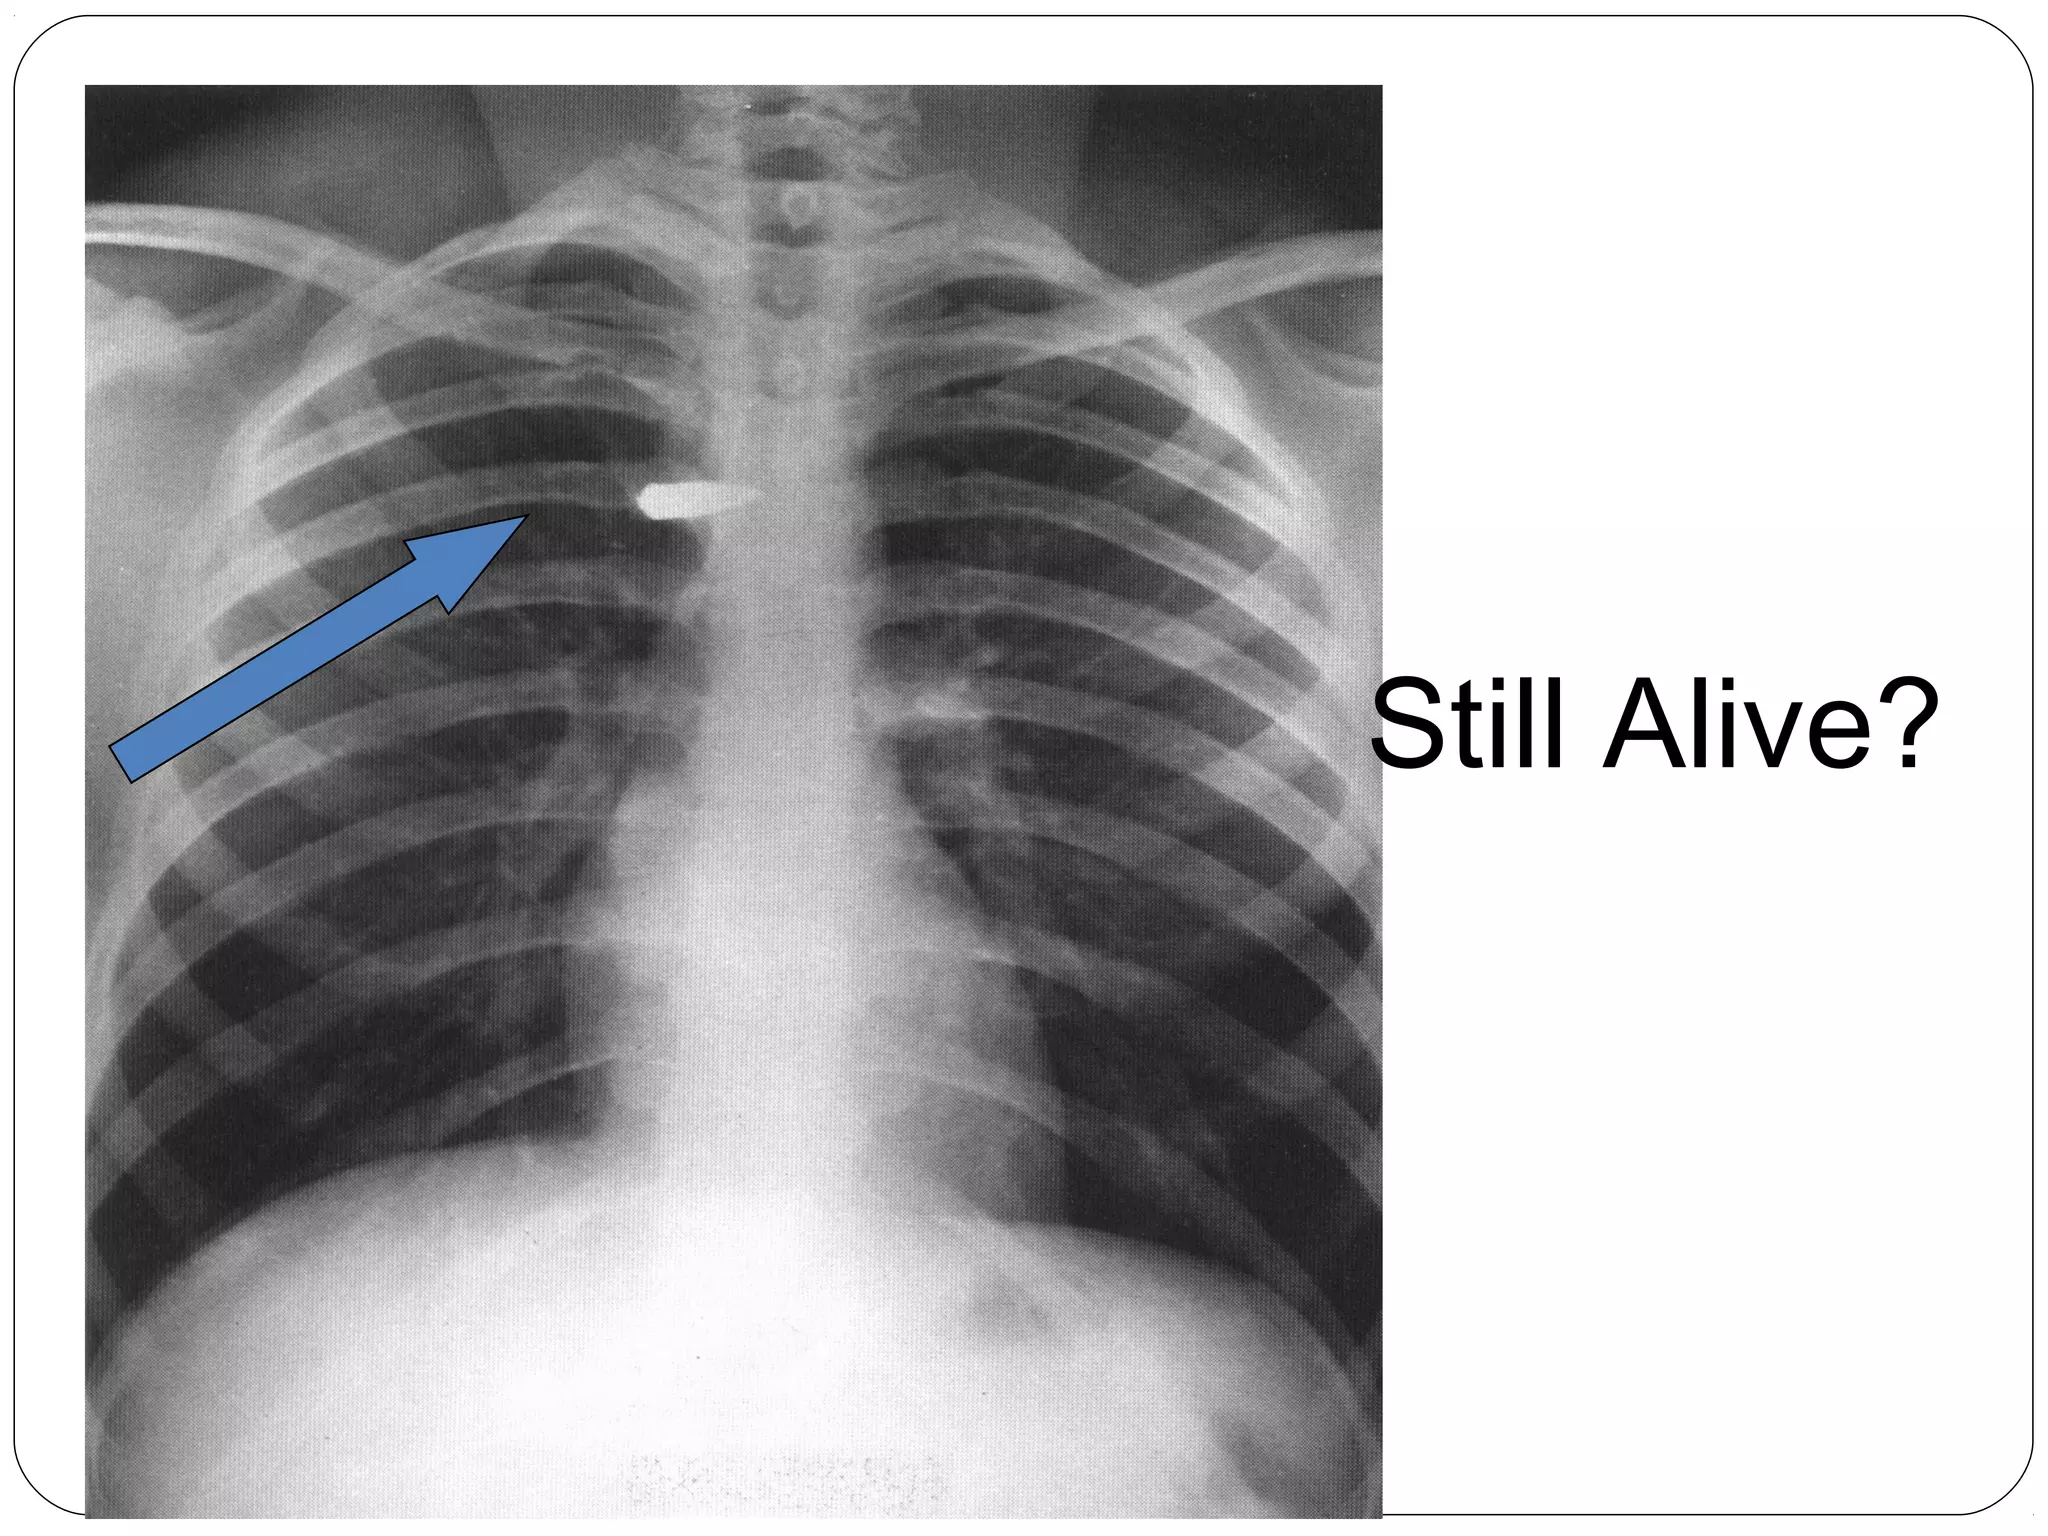

Still Alive?

…That was

close

Bullet can be in

any of these places

(anterior to

posterior at same

level)

1 - spinal cord

2 - trachea

3 – Superior

Vena Cava

4 - aorta

Viewing Images